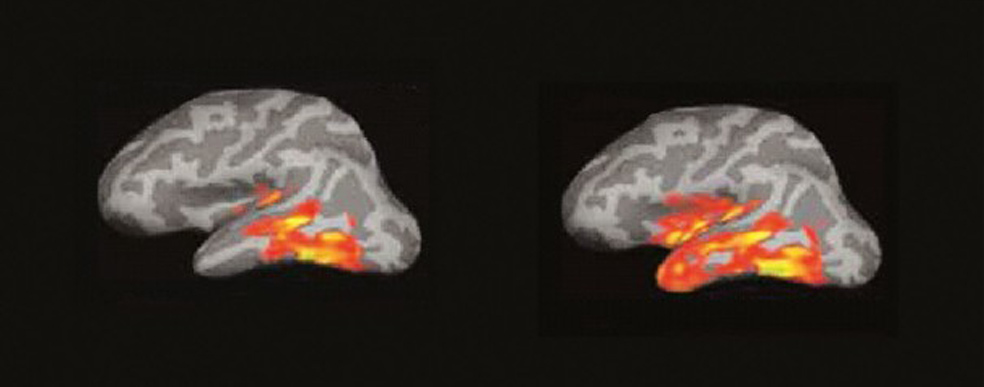

Entre 250 y 460 milisegundos. (A la izquierda) 3. Se produce una explosión de actividad en múltiples áreas de las regiones temporal y frontal del hemisferio izquierdo. El cerebro recopila todo lo que sabe de esa palabra. fonética, función sintáctica, significado… (A la derecha) 4. El ‘incendio’ se extiende, creando circuitos neuronales que conectan los procesos del lenguaje, visuales, espaciales… Comprendemos, sacamos conclusiones y surgen los recuerdos y los pensamientos propios.